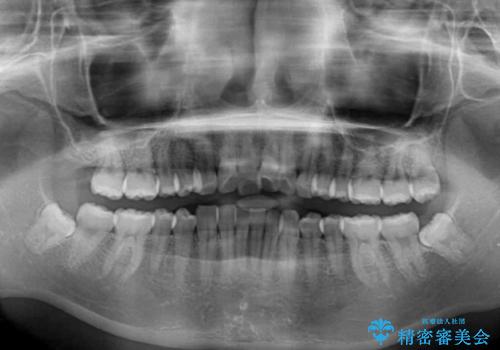

- 1本飛び出した前歯を治したいとのことで来院された患者様です。

歯列全体の拡大とIPR(歯と歯の間を削る)によってデコボコが解消するようにし、さらにゴムかけを活用して右側の咬み合わせ位置を変えるように設計し、インビザラインにより治療を行うこととしました。

後方移動に際し、上下顎の親知らずは3本とも抜歯することとしました。